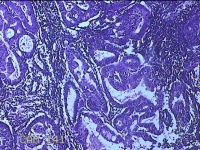

宫腔内容物

性别

女

年龄

46岁

临床诊断

异常子宫出血

一般病史

月经不规则半年,阴道不规则出血7天。

标本名称

大体所见

灰白暗红色不规则碎组织5.5x4.8x0.8cm一堆。

图2